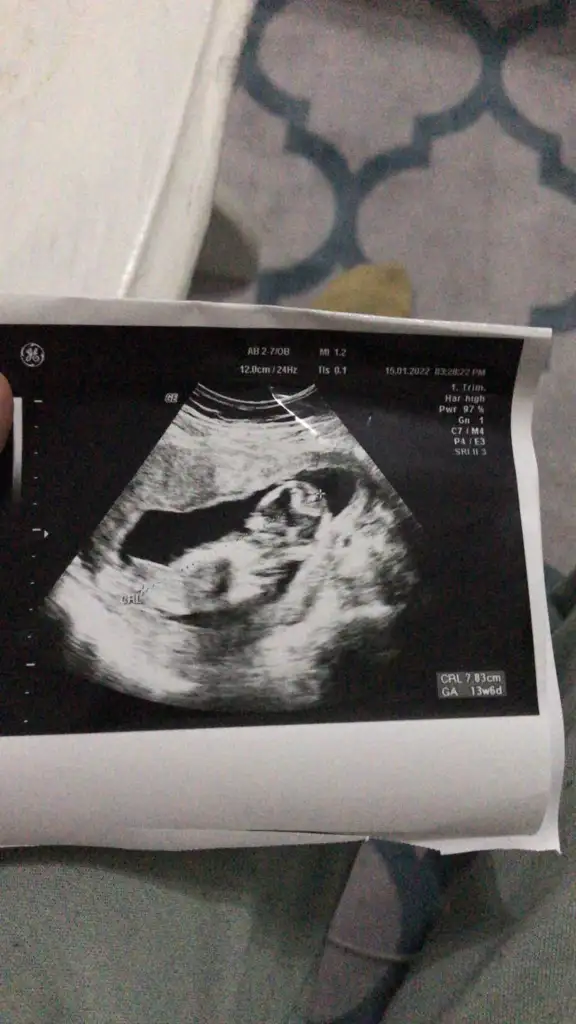

Sirti yukarda sagda kafasi var. Asagida agzi ve burnu var. Yan profil sanirim.

Demek ki var ben pek bişeye benzetemedimSirti yukarda sagda kafasi var. Asagida agzi ve burnu var. Yan profil sanirim.

Kemikler beyaz gorunur. Göz siyah yuvarlak mesela. Ben burnu var görüyorum. Doktor degilim sonucta ama bence varDemek ki var ben pek bişeye benzetemedim

Şu işaretledigim burun muKemikler beyaz gorunur. Göz siyah yuvarlak mesela. Ben burnu var görüyorum. Doktor degilim sonucta ama bence var

Indirip işaretledim telefonumdan silecegim göstermek amacli burasi burnu canimDemek ki var ben pek bişeye benzetemedim

Ağzı sanıyorum orayıIndirip işaretledim telefonumdan silecegim göstermek amacli burasi burnu canim

Onun alt kisminda girinti var o isaretledigim kemik burnu yani. Solunda agiz var. GirintiliAğzı sanıyorum orayı

Bu sanirim 13 haftalikken daha önceki bi ultrasom burda sirti asagida sirt üstü yatmiş pozisyonda yani. Kafası yine sağ tarafta.Bide bu var